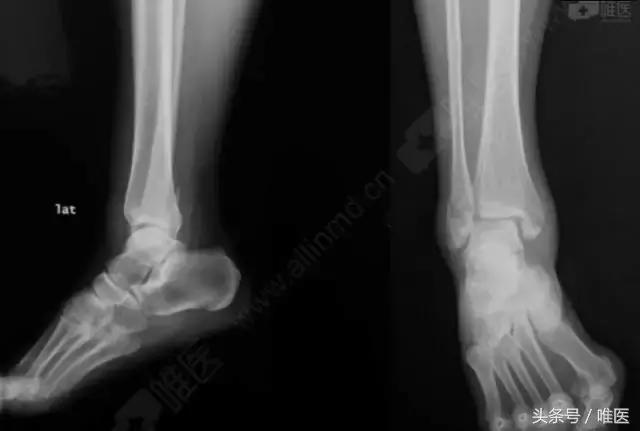

X线:右侧踝关节骨折

治疗前影像